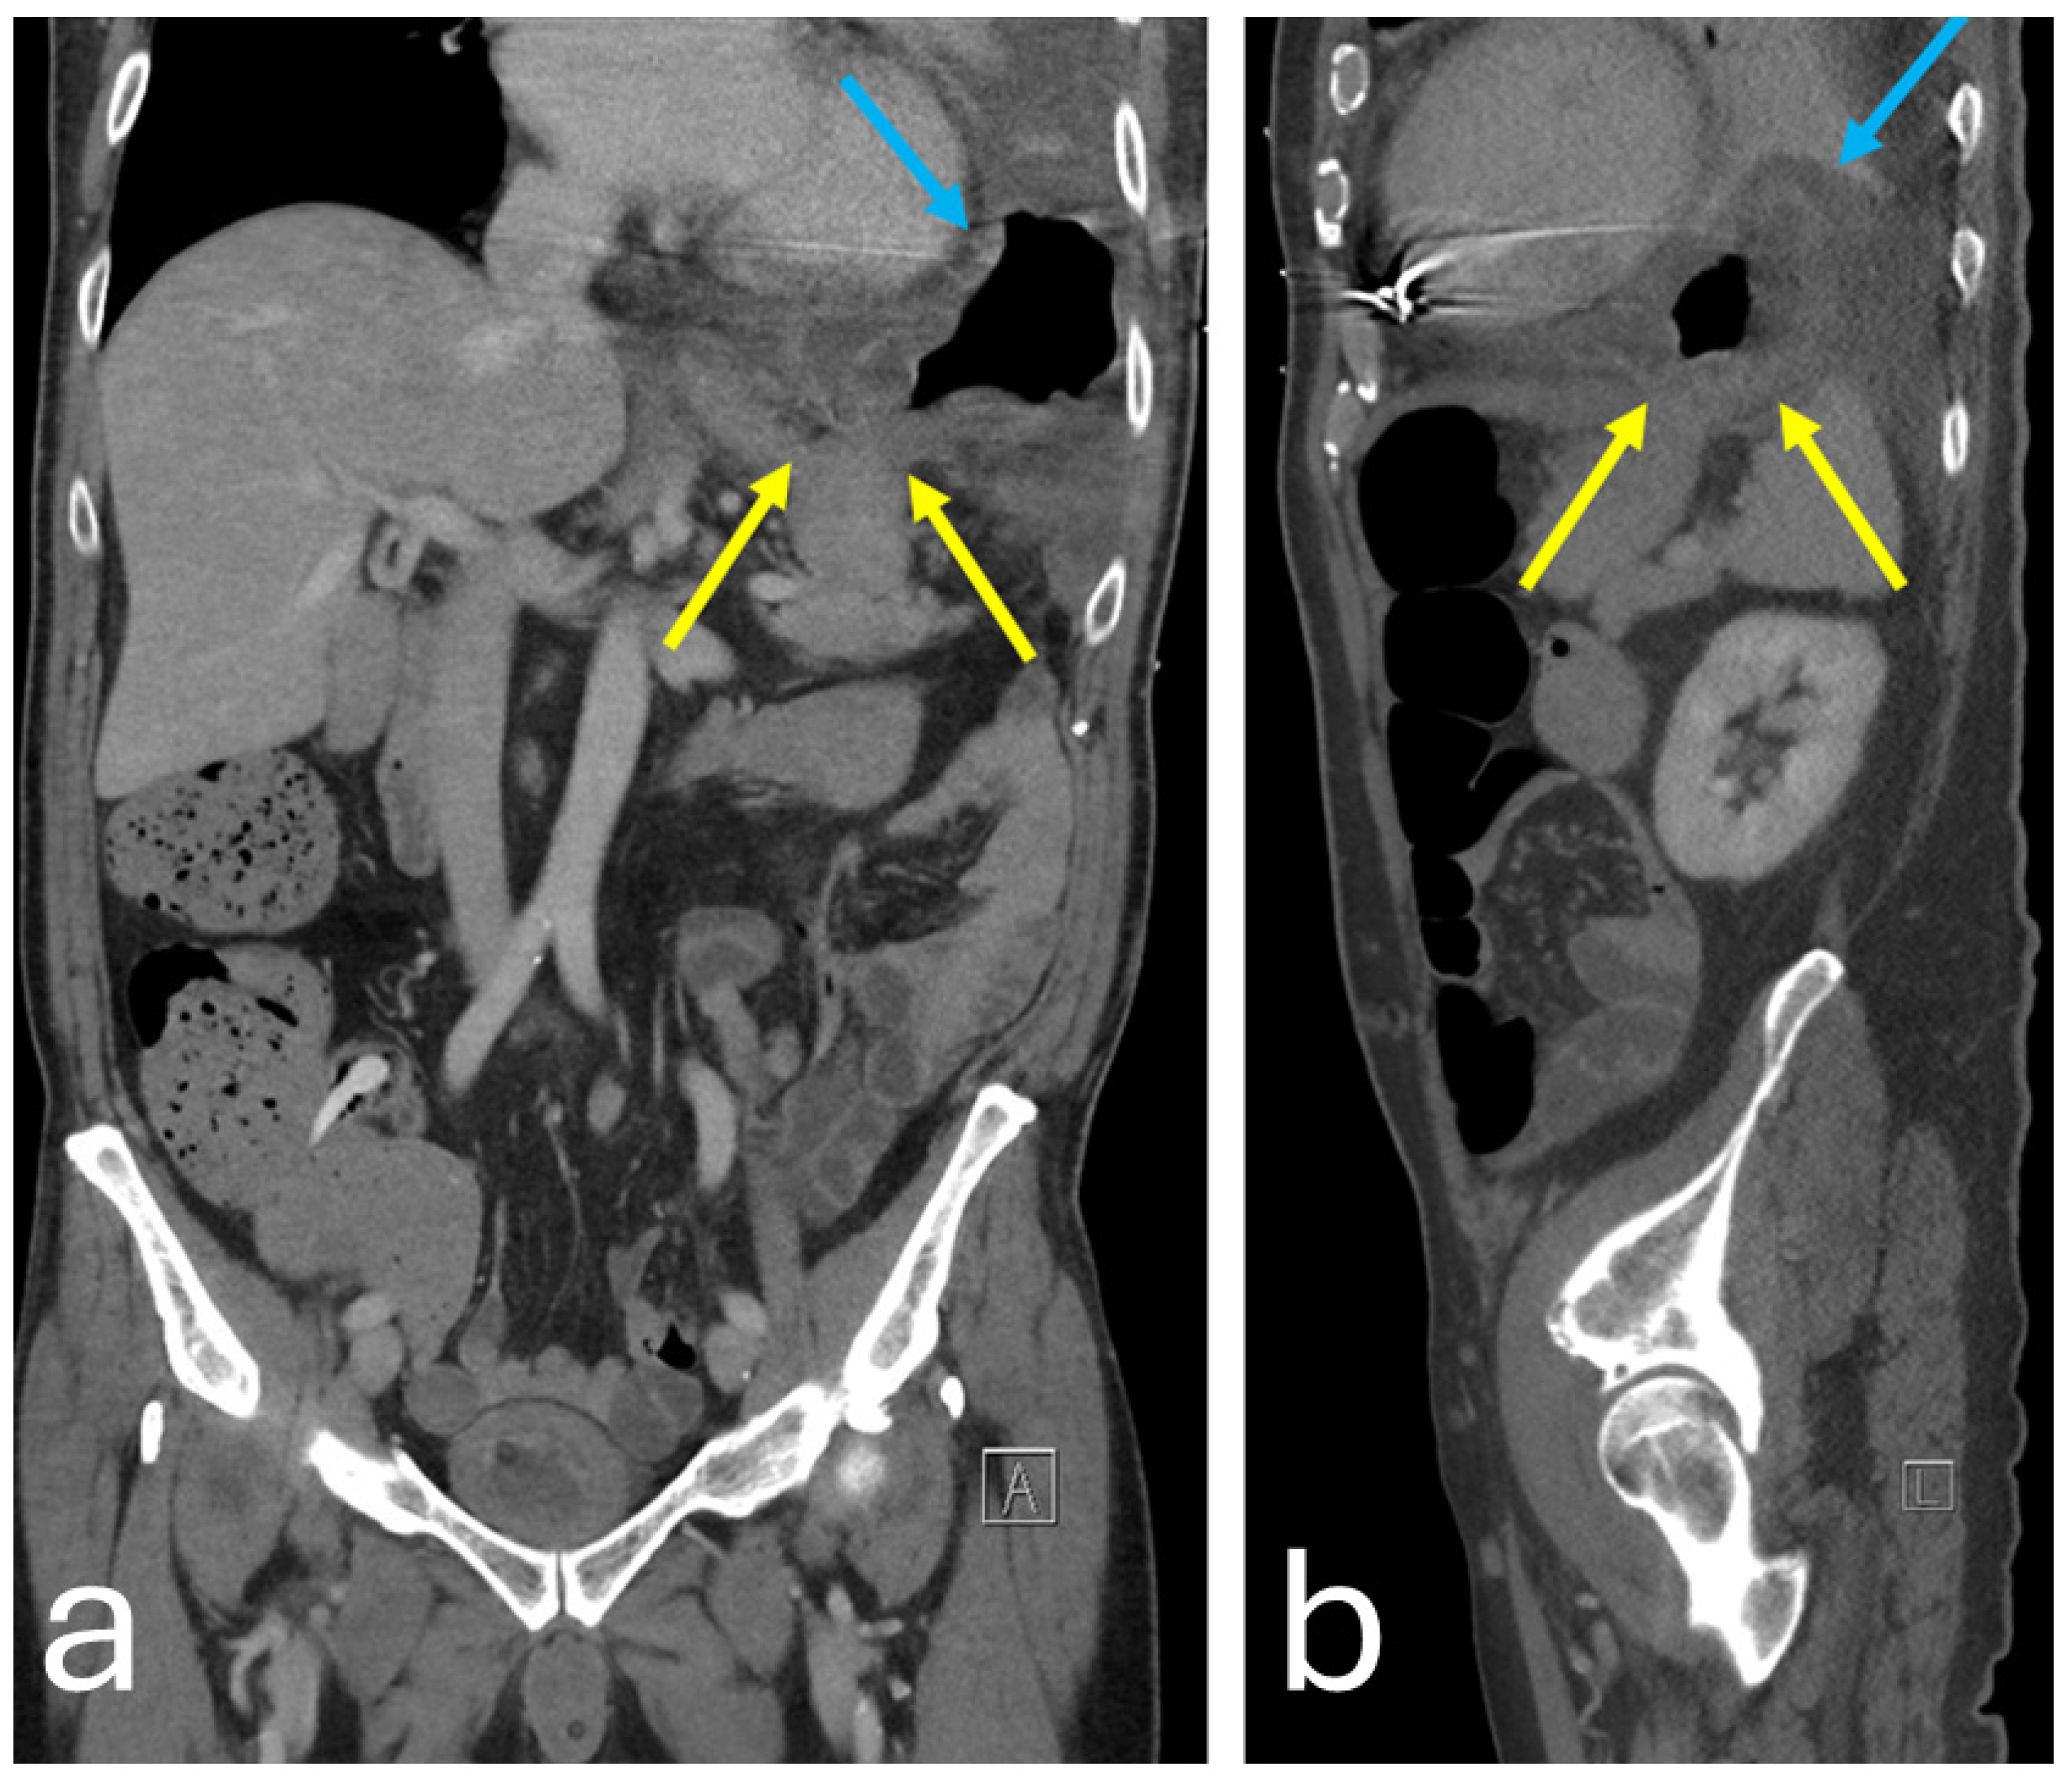

Chest–abdominal contrast-enhanced computer tomography (CT) demonstrated herniation of the gastric fundus into the thorax through discontinuation of the left diaphragmatic dome. The mucosa of the gastric fundus appeared thickened due to edema and delayed arterial enhancement compared with the remaining portions of the stomach, suggesting possible ischemic suffering (Figure 3).

Figure 3. CT scan of coronal (a) and sagittal (b) planes showing diaphragmatic laceration (yellow arrows) with incarcerated gastric fundus (blue arrows).